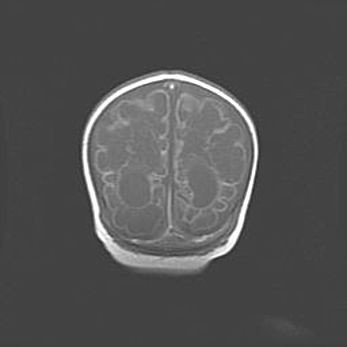

Ниже представлена  галерея МРТ снимков, полученных с применением LMT неонатальных матричных РЧ катушек. Также каждая группа МРТ снимков сопровождается информацией о пациенте (диагноз, возраст, вес, пол, срок гестации) и краткой сопроводительной расшифровкой диагноза.

Открытая гидроцефалия.

Возраст: 6 месяцев 15 дней

Вес: 6200 г

Пол: женский

Окружность головы: 41 см

Срок гестации: 38 недель

Гидроцефалия головного мозга у новорожденных – это скопление избыточного количества цереброспинальной жидкости в головном мозге. Ее избыточное скопление в мозге приводит к патологическому расширению желудочков мозга (четырех полостей, расположенных в глубине белого вещества мозга, заполненных цереброспинальной жидкостью и связанных узкими проходами).

Открытый тип гидроцефалии (сообщающаяся) наблюдается тогда, когда нарушен механизм всасывания ликвора в системный кровоток. При этом типе причиной заболевания чаще всего является перенесенные ранее инфекции (например: менингит),  либо же наличие крови в субарахноидальном пространстве.